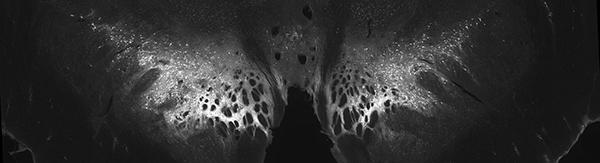

中脑冠状面标记染色的多巴胺神经元。这是研究人员记录信号的大脑区域。 (图片来源:Rothenhoefer等)